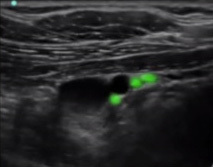

Bild: Regio infraclavicularis, laterale und posteriore Stränge

Markierter Bereich: Posteriore Stränge